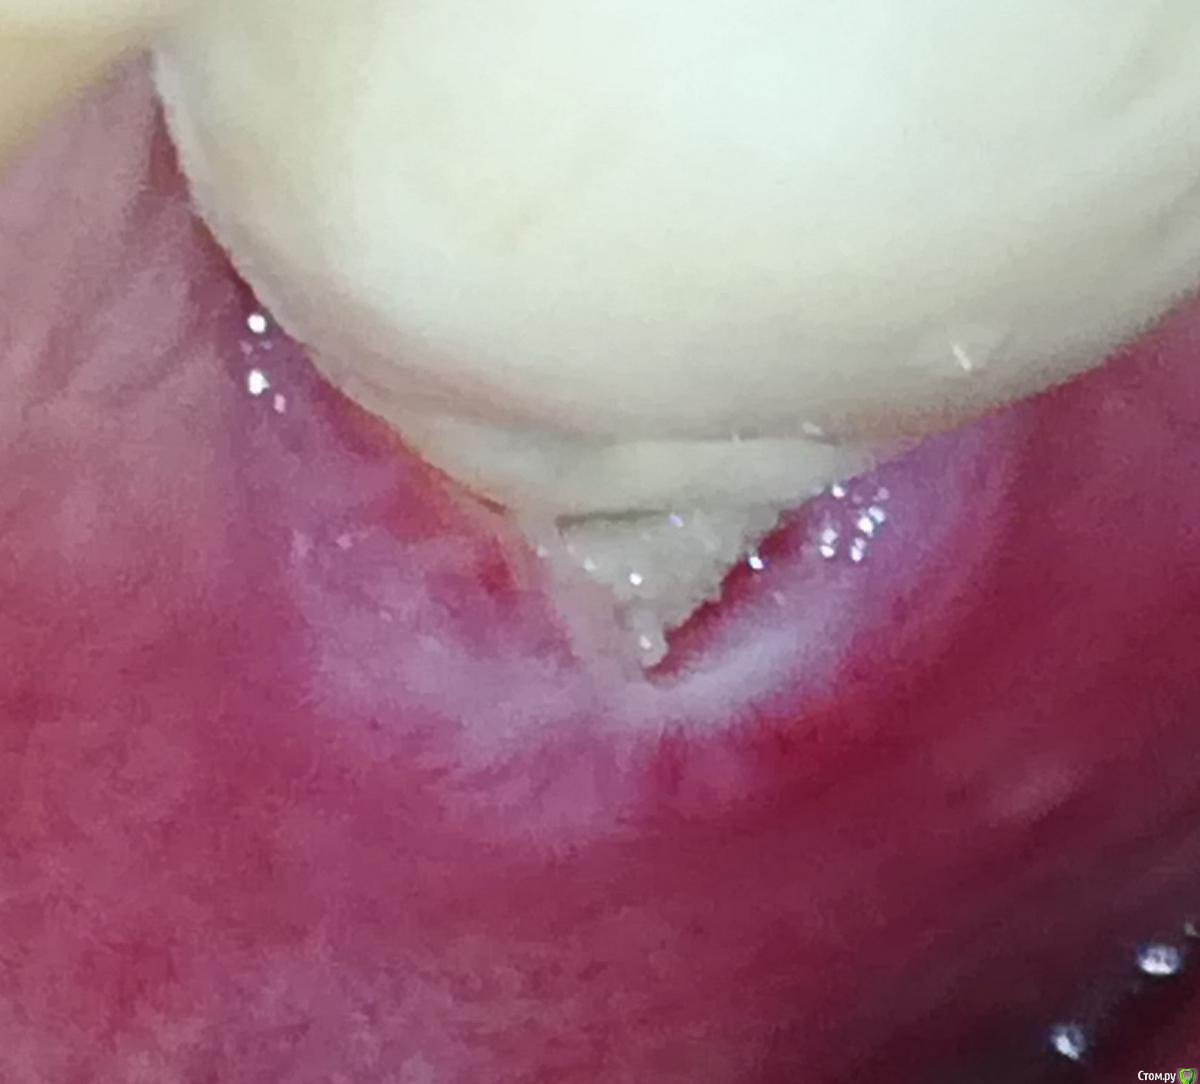

Alex19_73 Опубликовано 3 апреля, 2017 Автор Поделиться Опубликовано 3 апреля, 2017 Первую пластику десны сделали, фото ниже, на днях намечена вторая операция пластики десны.Но обнаружилась проблема в том месте в котором подозревал ее изначально. В четверг начал разглядывать десну со стороны языка и показалось подозрительным что ее край слишком светлый. Разглядел что в районе края десны на коронке какая то неоднородность, ощущение что она трет по десне и похоже десна уже несколько опустилась и вдобавок там не заживающая рана. Фото с кровью было сделано утром до чистки зубов, хотел сделать фотографию, но мешали пузырьки слюны, провел по десне языком и пошла кровь.Врачу еще об этом не говорил. Помогите пожалуйста определиться с тем что делать в такой ситуации, что просить у врача, что должен сделать врач. Коронка несъемная. Ее можно только распилить. Ссылка на комментарий

Alex19_73 Опубликовано 3 апреля, 2017 Автор Поделиться Опубликовано 3 апреля, 2017 здесь наверно лучше видно структуру этого фрагмента , что типа "грозди" Ссылка на комментарий